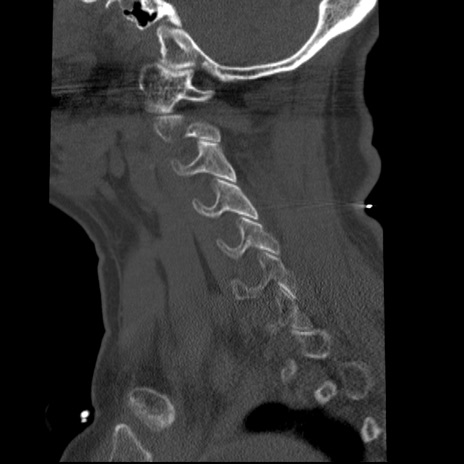

症例50 頚椎CT(矢状断像)

異常所見と診断は?

頚椎CT